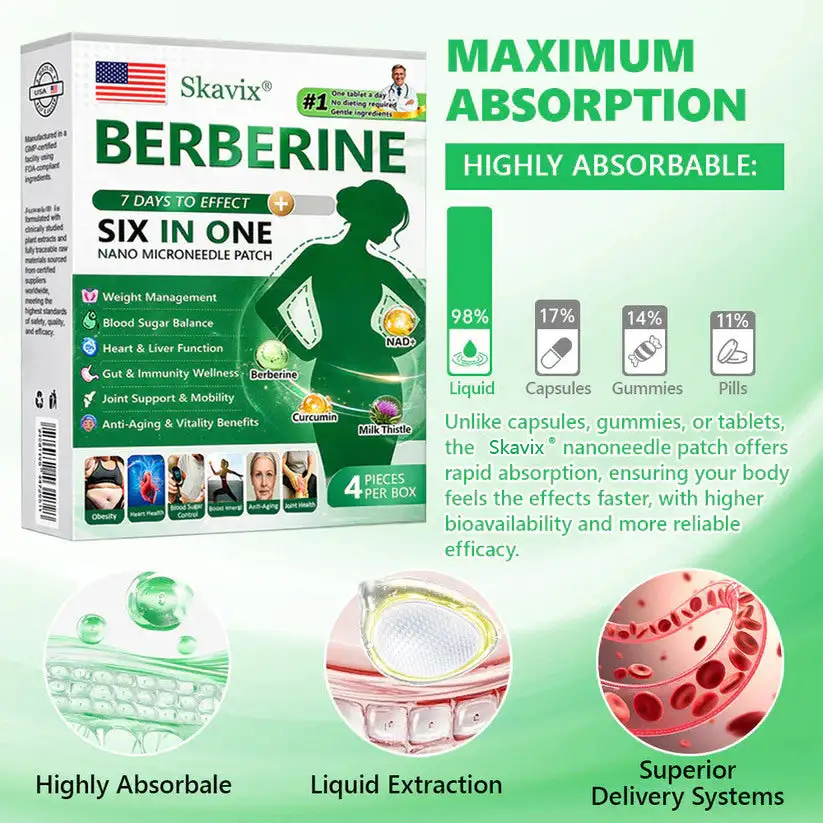

What if one simple patch a day could help you feel more balanced, refreshed, and comfortable in your everyday life — without complicated routines? That’s exactly what Skavix® Berberine 6-in-1 Nano Microneedle Patch is designed for. With advanced nano microneedle technology and carefully selected ingredients, the patch works gently throughout the day to support daily balance and overall wellbeing. Many people notice that over time they feel more refreshed, more comfortable in their body, and more confident in their daily life. Sometimes a small daily habit can make a meaningful difference.

Pain-Free Active Delivery

Each needle is0.27mmlong, just1/7the thickness of a hair, and made from a dissolvable medication. These microneedles are precision-engineered using the latest manufacturing techniques to ensure a seamless, pain-free experience while effectively delivering active ingredients directly into the skin.